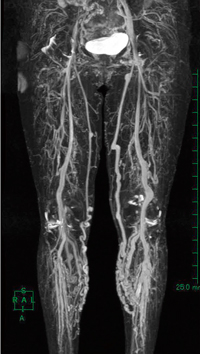

●下肢静脈領域

非造影下肢静脈撮像にも,当院は3D Delta Flowを用いている。先にも述べたように,3D Delta Flowは心拡張期と心収縮期の撮像を行っており,そのうち心収縮期は,動脈血流の流速が速いためflow voidとなり,静脈のみが描出されていることになる。つまり心収縮期データのみを用いれば,下肢静脈画像が作成可能ということになる。しかし,当院使用のMRI装置では心拡張期と心収縮期のデータは1つのシリーズ内にあり,奇数枚数目が心収縮期,偶数枚数目が心拡張期となっているため,MRI装置本体にて心収縮期のみを選択することは現実的ではない。

AZE VirtualPlace Plusのデータ選択領域を見てみると,画像選択方法に「1枚おきに」という方法があり(図6),心拡張期と心収縮期のデータをAZE VirtualPlace Plusへ転送して「1枚おきに」を選択し,奇数枚数目のみを選択する(図7)。すると,心収縮期データのみを,わずか3クリックで選択可能である。下肢静脈も下腿全長を3分割にてMR venography(MRV)撮像を行っているため,同様に3ステップ分を選択し,画像のつなぎ合わせ作業を行っている(図8)。

図8 非造影下肢MRV

全長つなぎ合わせ画像